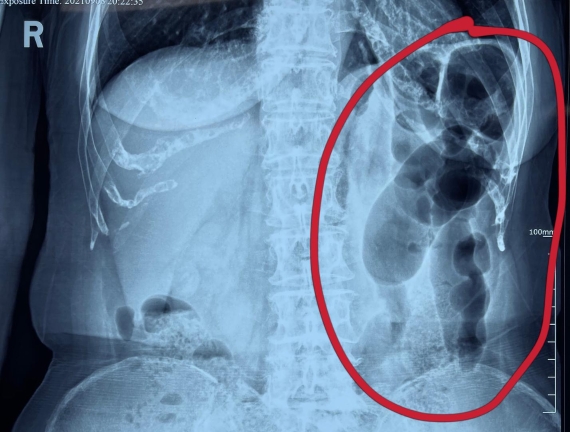

據(jù)省醫(yī)院消化病院消化二科姜子曄醫(yī)生介紹,韓大娘今年已經(jīng)73歲,家住哈爾濱市,一周前開始腹脹腹痛,有較為明顯的左側(cè)腹部疼痛,疼痛劇烈時(shí)會(huì)出現(xiàn)左側(cè)腹部鼓包情況,排氣排便后有所好轉(zhuǎn)。韓大娘家人見(jiàn)狀將其送到了黑龍江省醫(yī)院,門診檢查腹部平片提示為左側(cè)腹部積氣,口服全消化動(dòng)力藥及通便治療后腹痛腹脹有所緩解,入院前再次突發(fā)左側(cè)腹痛加重伴有明顯腹脹,急診隨后以“腹痛腹脹原因待查”將韓大娘收入到消化病院消化二科。

姜子曄醫(yī)生熱情接待了韓大娘,為其進(jìn)行了仔細(xì)查體,除了左側(cè)腹部壓痛并未見(jiàn)明顯異常,對(duì)癥給予灌腸后,韓大娘的腹脹有所緩解,第二天姜子曄醫(yī)生為韓女士進(jìn)行了胃腸鏡檢查,也未見(jiàn)明顯異常。但此時(shí)韓大娘腹部平片結(jié)腸腸管擴(kuò)張仍然很嚴(yán)重,腹痛腹痛也沒(méi)緩解,到底什么原因呢?消化二科主任陸以霞在查房時(shí)建議繼續(xù)給予韓大娘口服全消化動(dòng)力藥,必要時(shí)灌腸治療,同時(shí)陸以霞主任在追問(wèn)病史查體時(shí)發(fā)現(xiàn)韓大娘左下腹紅色皮疹和小水泡,反復(fù)抓撓腹部皮膚部分已結(jié)痂,高度懷疑為帶狀皰疹。